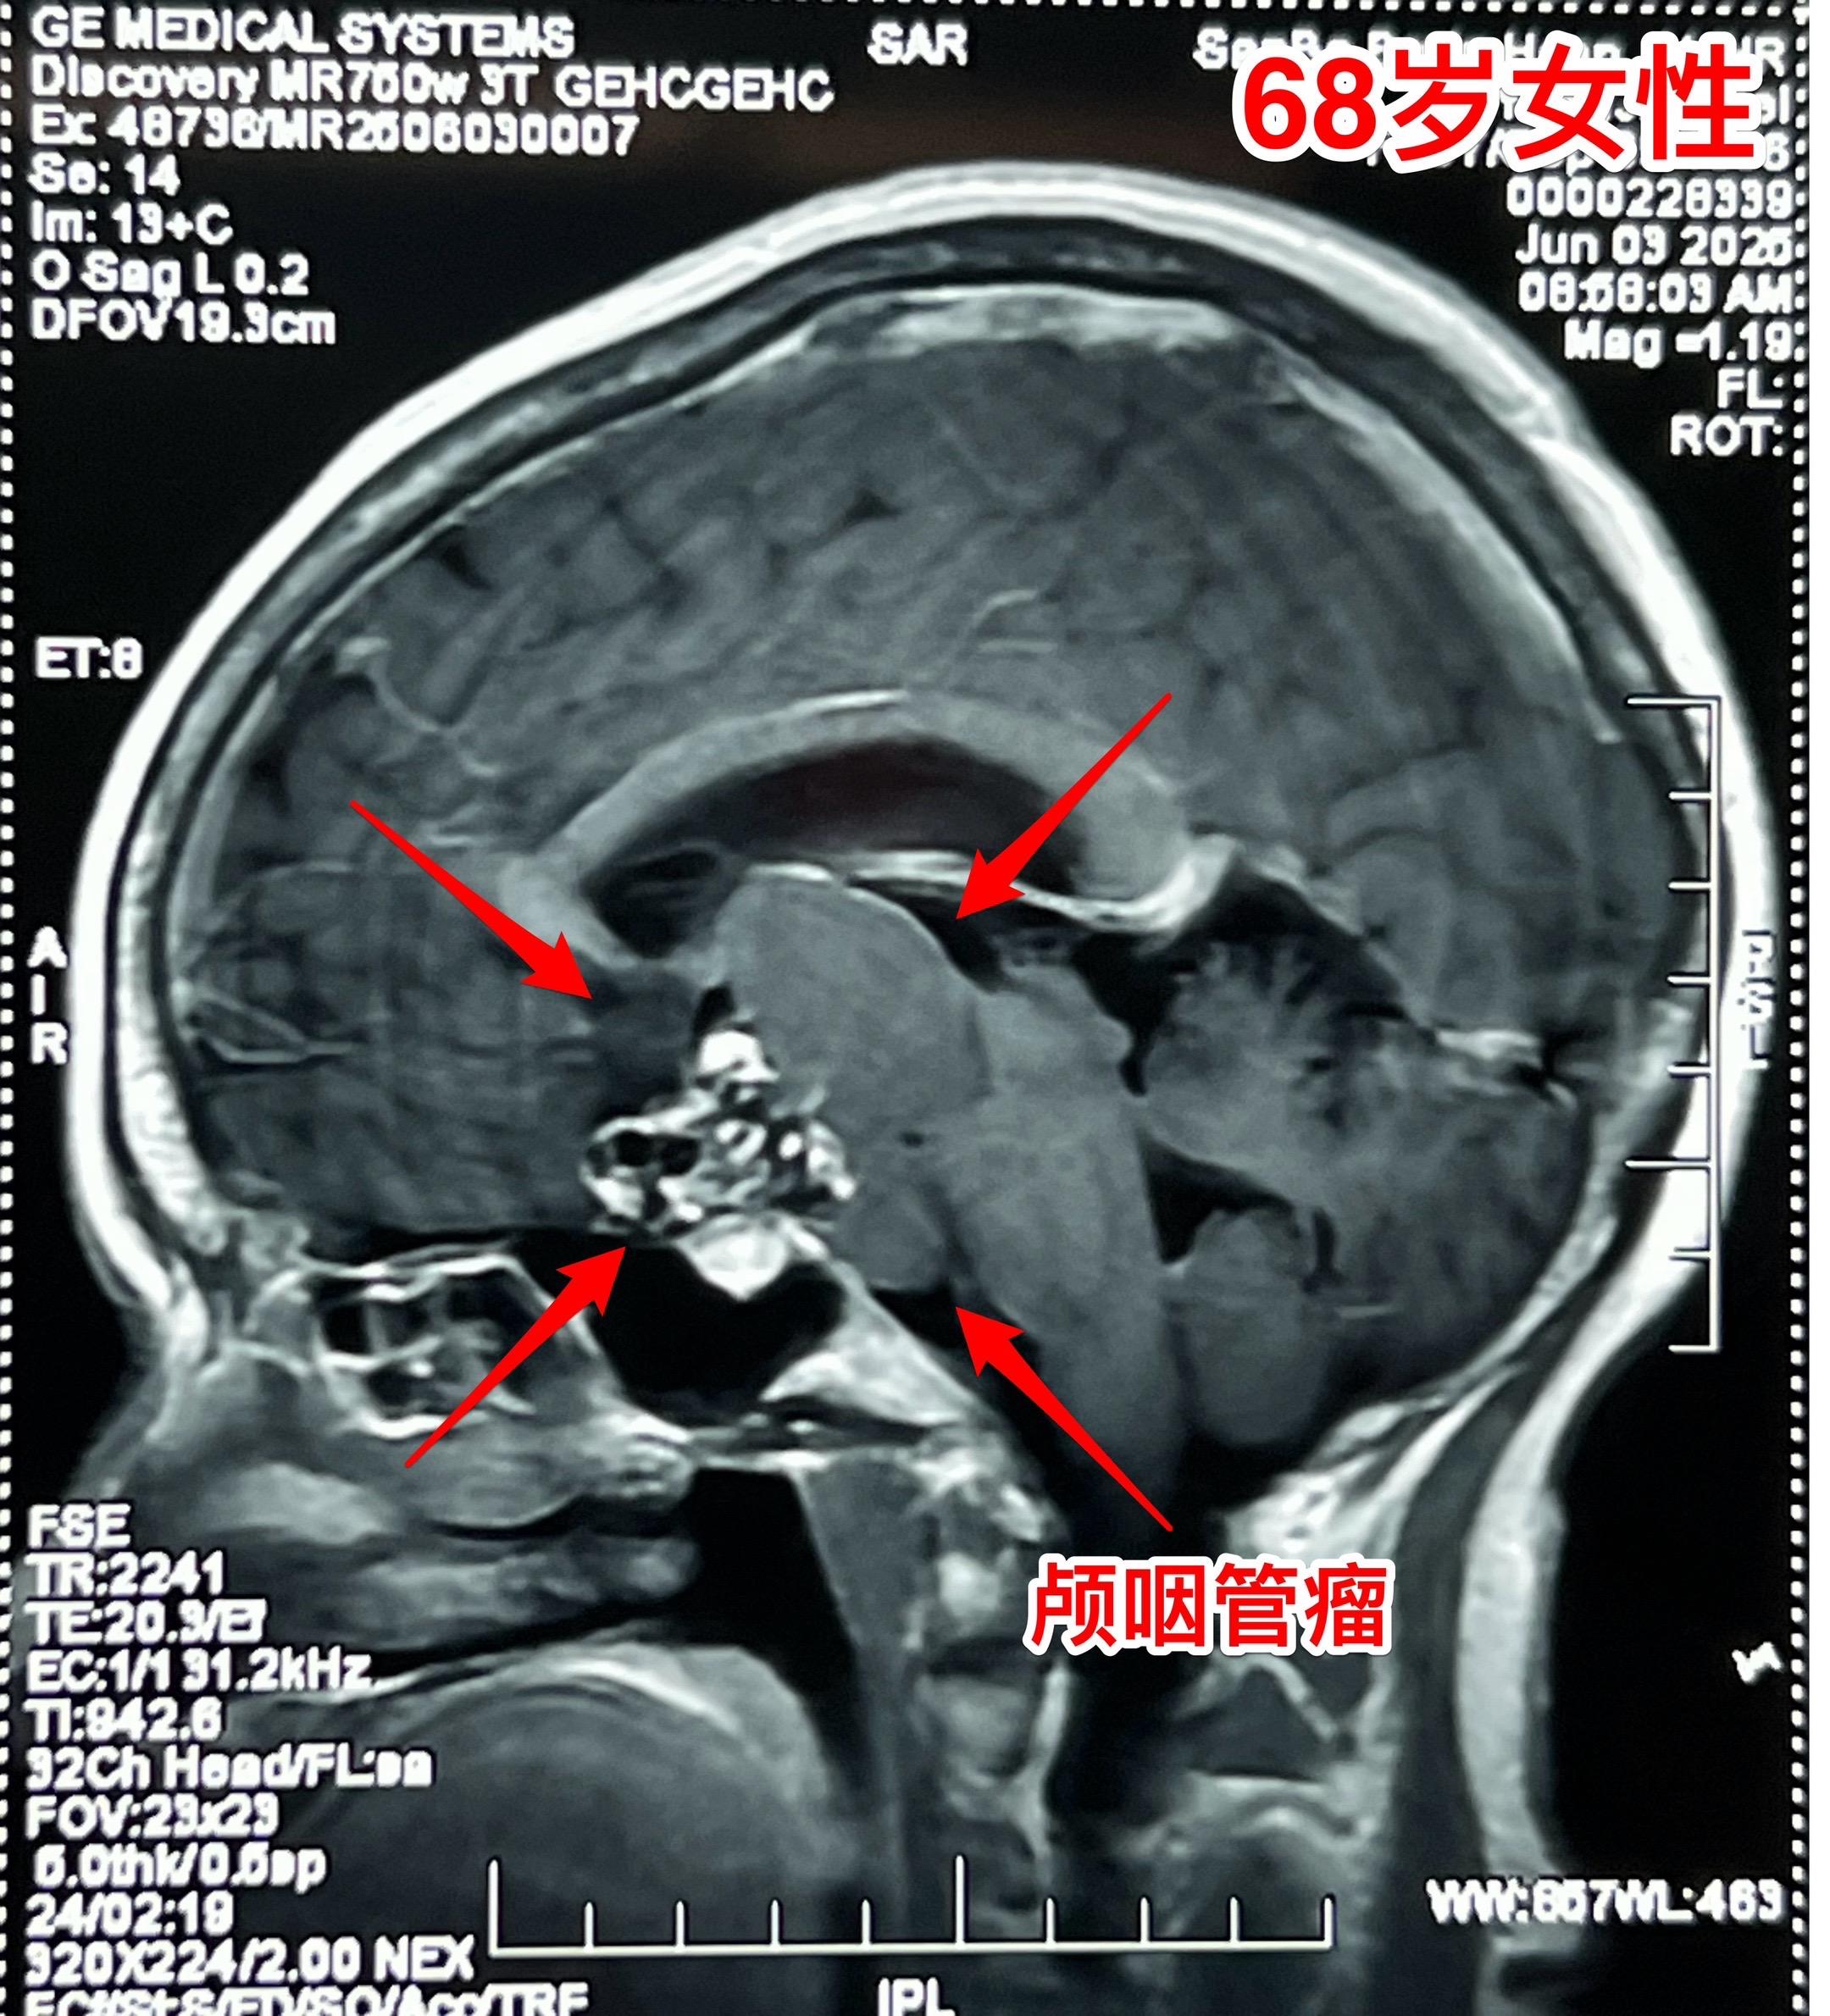

68岁老人患颅咽管瘤是否可以作手术? 颅咽管瘤并非小孩子的病,老年人也可以患颅咽管瘤。 过去十年间我科治疗过颅咽管瘤患者共计1153例次,其中53例患者年龄在60-74岁。 所以,老年人患颅咽管瘤也不是手术禁忌。 这个68岁南通市女病人因颅咽管瘤造成视力下降、头晕症状,住院前一天出现反复呕吐症状,提示颅内压升高,所以应该尽早作手术,否则会造成生命危险。2025年6月8日作了开颅手术,颅咽管瘤得到完全切除。幸运的是垂体柄受肿瘤侵蚀的不严重,得以保留。今天是手术后第